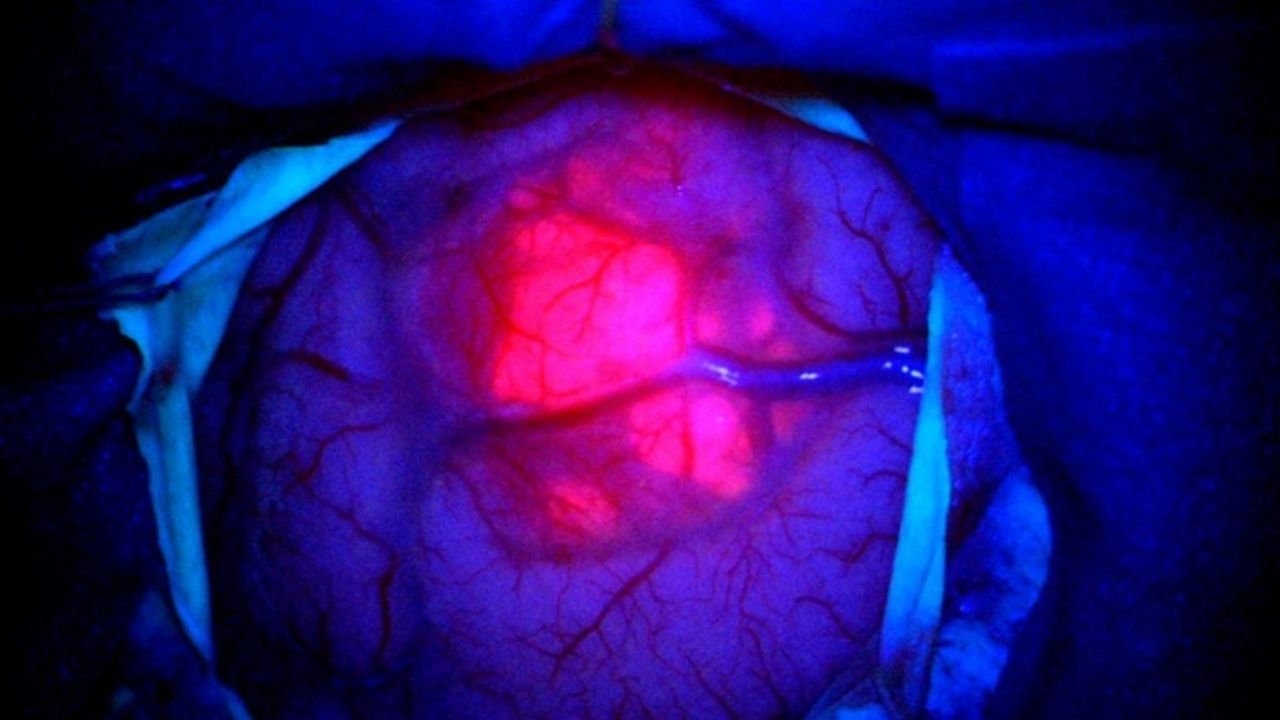

A Unimed Litoral passou a utilizar, em procedimentos de neurocirurgia de precisão, a tecnologia de visualização por fluorescência, que emprega o corante (ácido 5-aminolevulínico – 5-ALA) aliado a luzes especiais que fazem as células doentes “brilharem” ao microscópio. O recurso permite ao cirurgião identificar com maior precisão as áreas tumorais.

Essa inovação contribui para maior precisão na remoção de tumores, especialmente quando localizados em regiões profundas ou próximas a áreas cerebrais críticas, reforçando o avanço da saúde e da inovação no setor.